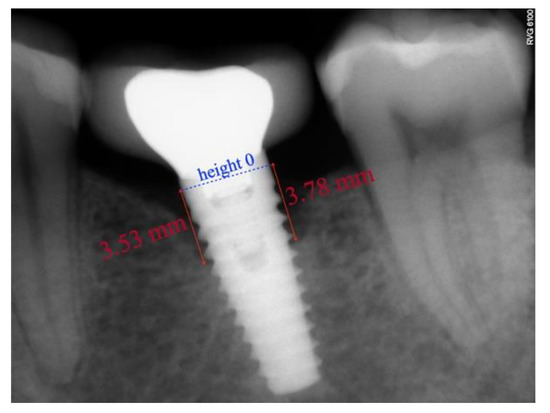

2.3. Radiographic Technique and Bone Loss Measurement Method